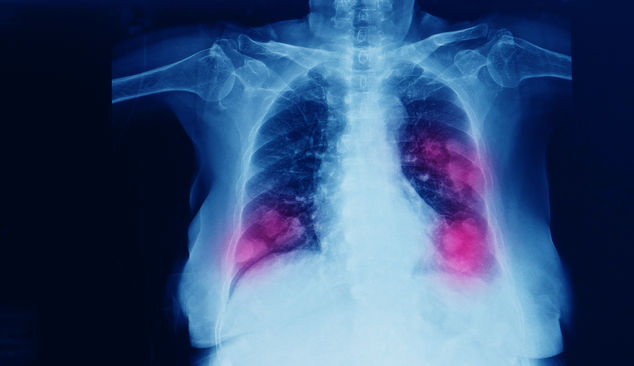

AKCİĞER KANSERİNİN BAŞLICA SEBEBİ TÜTÜN VE TÜTÜN ÜRÜNLERİ

Prof. Dr. Kutluk, en sık görülen türler içerisinde yer alan akciğer kanserinin başlıca sebebinin tütün ve tütün ürünleri kullanımı olduğuna işaret ederek sözlerini şöyle sürdürdü: "Dünyada yılda yaklaşık 2 milyon akciğer kanseri vakası görülüyor. Yılda yaklaşık 2 milyon kişi de meme kanserine yakalanıyor. Bunları kalın bağırsak, prostat, mide ve karaciğer kanseri takip ediyor. Türkiye'de de durum çok farklı değil. Ülkemizde yılda ortalama 41 bin akciğer, 24 bin de meme kanseri vakası görülüyor. Yıllık öngörüler bu şekilde.